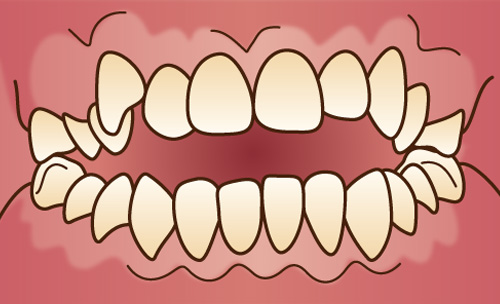

下顎が上顎よりも前に突き出ている状態で、横顔がしゃくれたように見えます。かみ合わせが反対になるので「反対咬合」、あるいは「受け口」とも呼ばれています。